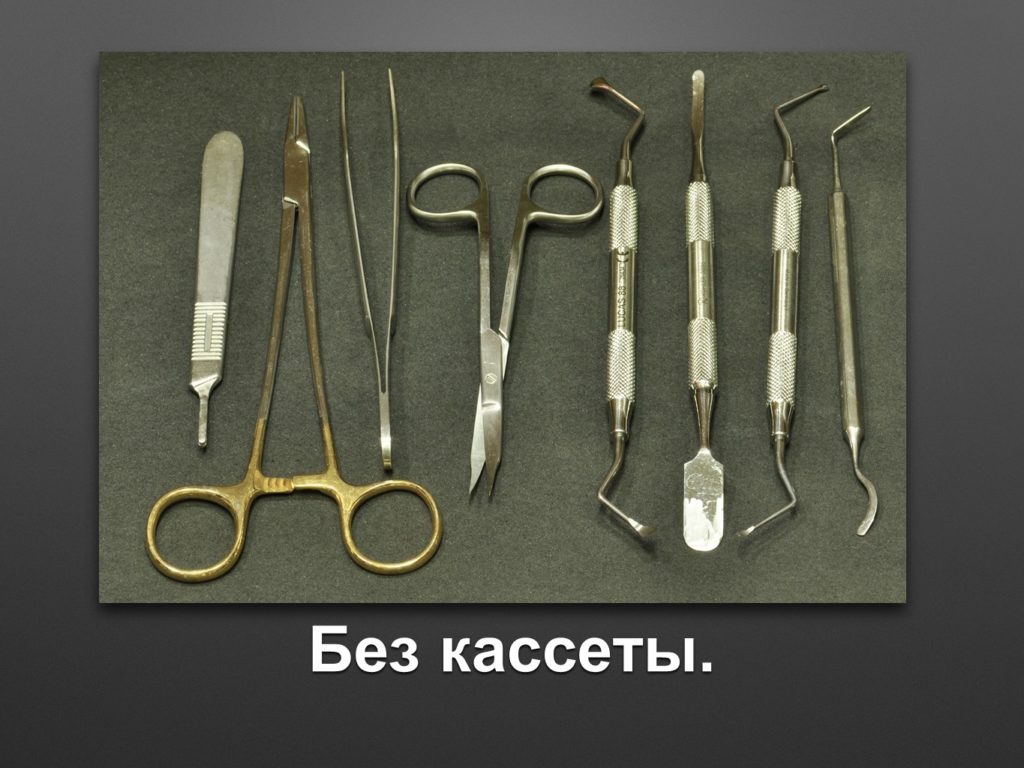

"Выстраданные" наборы инструментов

Все ниже перечисленные инструменты можно приобрести на сайте kohlermed.ru или связаться с нашим менеджером по тел 499-5179401

Все ниже перечисленные инструменты можно приобрести на сайте kohlermed.ru или связаться с нашим менеджером по тел 499-5179401